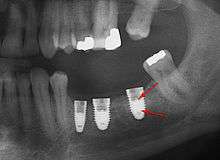

From these theoretical risks, derive the real world complications. Long-term failures are due to either loss of bone around the tooth and/or gingiva due to peri-implantitis or a mechanical failure of the implant. Because there is no dental enamel on an implant, it does not fail due to cavities like natural teeth. While large-scale, long-term studies are scarce, several systematic reviews estimate the long-term (five to ten years) survival of dental implants at 93–98 percent depending on their clinical use.[1][2][3] During initial development of implant retained teeth, all crowns were attached to the teeth with screws, but more recent advancements have allowed placement of crowns on the abutments with dental cement (akin to placing a crown on a tooth). This has created the potential for cement, that escapes from under the crown during cementation to get caught in the gingiva and create a peri-implantitis (see picture below). While the complication can occur, there does not appear to be any additional peri-implantitis in cement-retained crowns compared to screw-retained crowns overall.[40] In compound implants (two stage implants), between the actual implant and the superstructure (abutment) are gaps and cavities into which bacteria can penetrate from the oral cavity. Later these bacteria will return into the adjacent tissue and can cause periimplantitis. As prophylaxis these implant interior spaces should be sealed.[41]